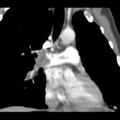

RADIOLOGY: CHEST: Case# 34548: NORMAL STUDY. A 40 year-old left hand dominant male presents with complaints of left arm pain and left hand numbness when the left arm is in certain positions.